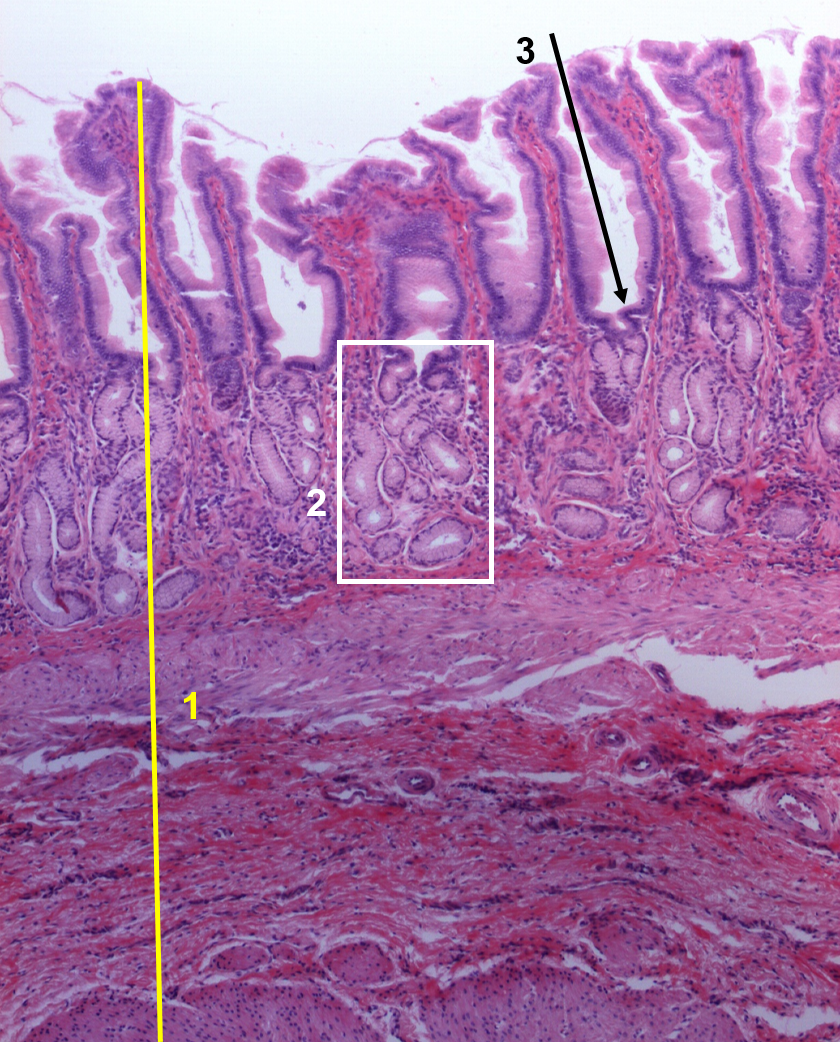

1: Estômago / Pilóro

2: Glândulas pilóricas

3: Fosseta